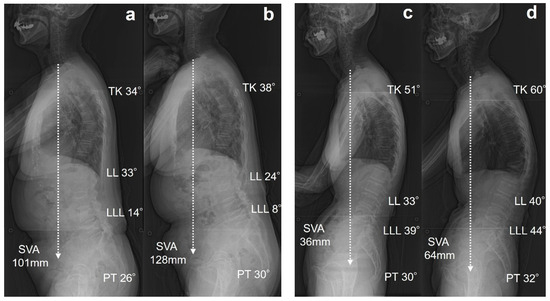

| Variable | Group N | Group M | Group S | p-Value |

|---|---|---|---|---|

| TK (°) | 31.6 ± 14.9 | 34.7 ± 16.0 | 40.9 ± 19.8 | 0.25 |

| TLK (°) | 20.5 ± 9.1 | 22.6 ± 14.4 | 22.5 ± 13.5 | 0.83 |

| LL (°) | 39.7 ± 12.4 | 34.4 ± 11.5 | 26.9 ± 23.3 | 0.05 |

| LLL (°) | 33.2 ± 7.0 | 26.9 ± 10.2 | 23.3 ± 12.9 | 0.01 * |

| PI (°) | 54.2 ± 7.9 | 49.2 ± 10.2 | 49.7 ± 7.2 | 0.14 |

| PT (°) | 24.3 ± 7.2 | 24.6 ± 7.6 | 29.1 ± 17.9 | 0.33 |

| PI-LL (°) | 14.4 ± 12.0 | 14.8 ± 13.2 | 22.7 ± 25.1 | 0.24 |